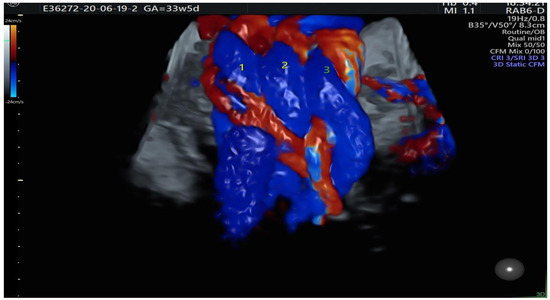

| Color Doppler |